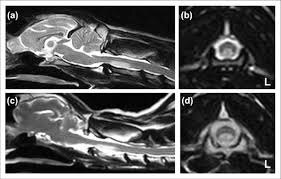

У кошек с предполагаемым острым инфарктом описаны очаги T1 iso/гипоинтенсивные и T2 гиперинтенсивные, иногда с мягким контраст‑усилением; при отсутствии другой системной патологии FCE рассматривается как вероятная этиология.

Для собак детально описаны МР‑находки у пациентов с предполагаемыми инфарктами/ишемической миелопатией и FCEM.

AVM/AVF (подозрение по МРТ)

Паттерны, заставляющие думать о сосудистой мальформации:

• “серпигинозные” сосудистые структуры/flow‑voids,

• диффузный отёк/миелопатия на фоне венозной гипертензии,

• сопутствующая костная гиперостоз/ангиоматоз (в отдельных фенотипах).

Для собак роль CTA и интервенционной ангиографии описана в конкретном клиническом случае экстрадуральной AVF, а интрамедуллярная AVM описана как антемортем диагностируемая по MRI+CTA.